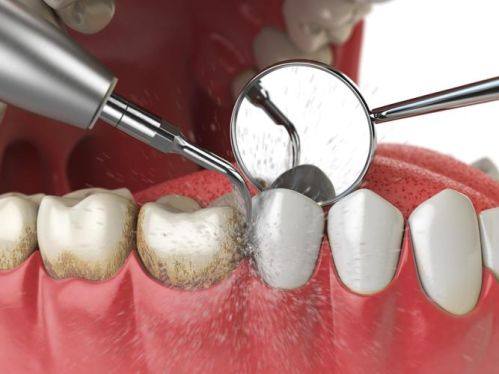

对于大部分人来说,洗牙(龈上洁治)间隔半年或一年洗一次比较好。这是因为在日常生活中,我们的牙齿表面会不断地积累牙菌斑和食物残渣。即使我们每天认真刷牙,也特别难完全清除这些物质。随着时间的推移,牙菌斑会逐渐钙化形成牙石,牙石不仅会影响牙齿的美观,还会刺激牙龈,引发牙龈炎、牙周炎等口腔疾病。

半年到一年的时间,牙齿表面积累的牙菌斑和牙石量通常会达到一个需要清理的程度。此时进行洗牙,可以有效地去除牙石和牙菌斑,预防口腔疾病的发生。而且这个频率也比较符合大多数人的生活节奏和口腔卫生状况,既不会因为洗牙过于频繁对牙齿造成不必要的损伤,也不会因为间隔时间过长而导致牙石积累过多。